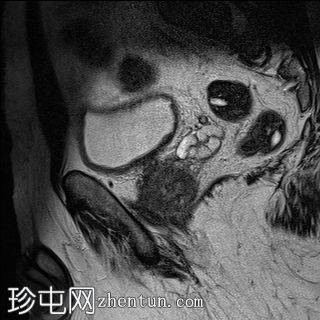

矢状位

T2加权像

外周带 (PZ):

T2WI:双侧外周带弥漫性、不均匀低T2信号,范围>15 mm,尖端后内侧可见小片相对保留的病灶。左侧尖端及腺体中部可见包膜隆起。评分5/5。

PI-RADS:5 - 极高风险(极有可能存在临床意义的癌症),考虑炎症性病变。

肉芽肿性前列腺炎是多参数磁共振成像 (mpMRI) 中一种重要的、与临床意义显著的前列腺癌相似的疾病,因为它可以产生明显的周围带异常,伴有扩散受限和早期强化,通常导致较高的 PI-RADS 分级。

在本病例中,mpMRI 显示双侧周围带弥漫性 T2 低信号,高 b 值 DWI/ADC 图像上呈扩散受限,早期强化阳性,并伴有包膜轮廓隆起。这种影像学表现可能类似于浸润性或广泛性周围带癌,尤其是在 PSA 升高和直肠指检异常的情况下。然而,炎症性疾病,特别是肉芽肿性前列腺炎,可能出现类似的影像学表现。经直肠前列腺活检的组织病理学检查显示,患者患有严重的慢性非干酪性肉芽肿性前列腺炎,未见肿瘤证据。